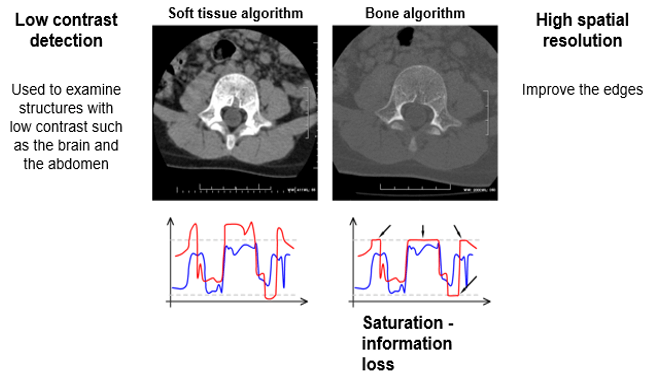

Low contrast detection is used to examine structures with low contrast such as the brain or the abdomen. This is accomplished by using higher kVp.

Spatial Resolution / Contrast

In areas such as the inner ear and the thorax, there are large differences in densities between very close structures. Using a wide window, there will be little visible noise in the image. Thus, the delivered dose could be low.

Low Contrast Resolution

The ability to distinguish between tissues with slight contrast differences is known as low contrast resolution. This is one of the advantages of CT and conventional radiography.